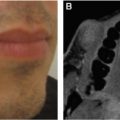

Fig. 10-1

The progression of an AVM is shown. This 6-year-old patient had a stage 1 lesion (A). At 29 years of age he has a stage 3 lesion (B).